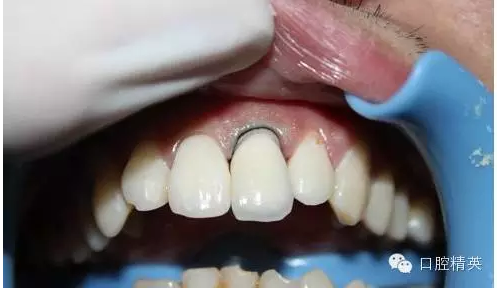

7:試戴烤瓷牙,鈷鉻瓷牙,瓷肩臺處理

8:頸緣檢查

9:完全就位

10:黏結(jié)后,側(cè)面觀

11:正面微笑圖